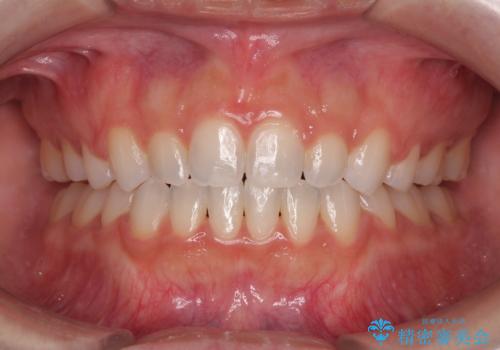

![[マウスピース矯正] 海外留学中でも可能な矯正治療の症例 治療後](https://seimitsushinbi.jp/wp/wp-content/uploads/2025/01/IMG_0074-500x350.jpg?v=1737343049)